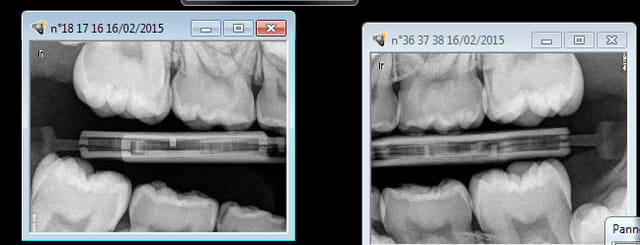

Je ne sélectionne pas mes patients sur les actes. Je fais les soins en 1 rendez vous en meme temps que les radios ( recommandées par La HAS 4 rétro coronaires ou 8 rétro alvéolaires en fonction du risque carieux et des antécédents de soins intensifs) et le détartrage ( 2- 3 soins max). Je dois dire que si il n'y a pas de prothèse à faire ca me fait bien chier de prendre un rendez vous supplémentaire pour les soins qui restent.

Tu veux un exemple ? ( pas trop importants les angles, pas eu le temps de prendre de photos, j'ai eu tort ?) faut speeder pour scorer en soins hein yobi ?

Ah ? il n'y avait pas de tartre sur celui là ! -)))))